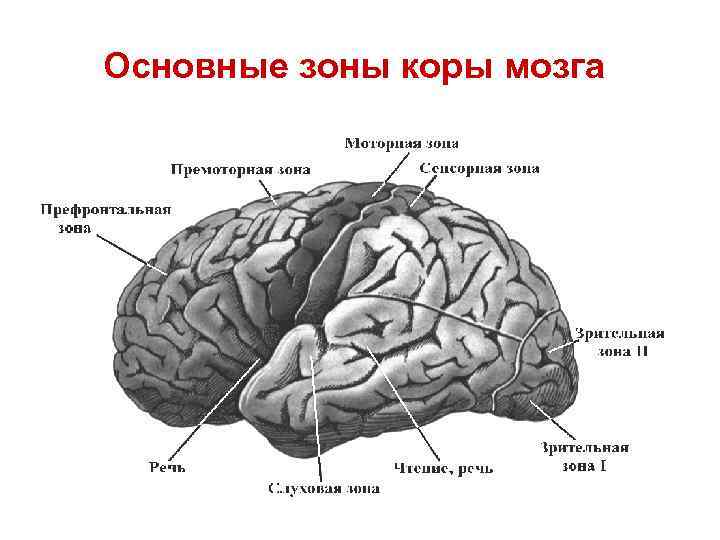

Схема чувствительных зон новой коры мозга